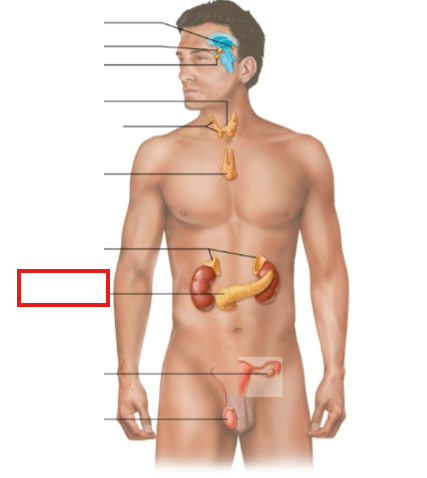

What structure is highlighted?

zona glomerulosa

What structure is highlighted?

zona fasciculata

What structure is highlighted?

zona reticularis

What structure is highlighted?

Capsule

What structure is highlighted?

medulla

What structure is highlighted?

pineal gland

What structure is highlighted?

hypothalamus

What structure is highlighted?

pituitary gland

What structure is highlighted?

thyroid gland

What structure is highlighted?

parathyroid glands

What structure is highlighted?

thymus

What structure is highlighted?

adrenal glands

What structure is highlighted?

pancreas

What structure is highlighted?

ovary (female)

What structure is highlighted?

testes (male)